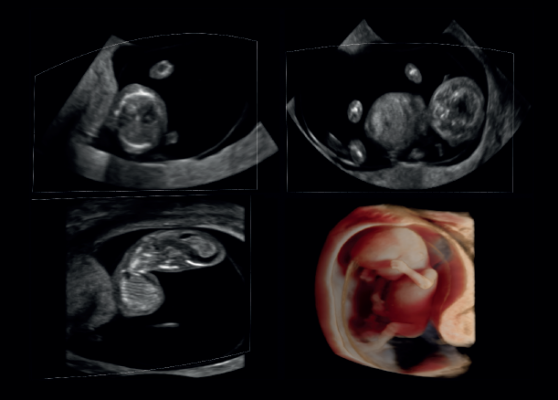

The software provides a new unique way of visualizing 3-D/4-D ultrasound images that improves image quality both in 3-D/4-D rendered images and in MPR views, enabling a clearer image and visualization of the fetus. The unique combination of 3-D volume enhancement in GOPiCE, scan conversion and rendering software results in high-quality images comparable to photos.

The ease of use of this visualization package allows for translucency adjustments, light source positioning, and skin softness and shading changes. The product delivers multiple views, including photographic view and versatile surface rendering view.

“Our photographic view offers further value to expecting parents. It also adds information to the clinician in fetal diagnosis,” sayid Anita Tollstadius, CEO of ContextVision. “We are confident that REALiCE will help ultrasound manufacturers make further advances within 3-D/4-D ultrasound.”